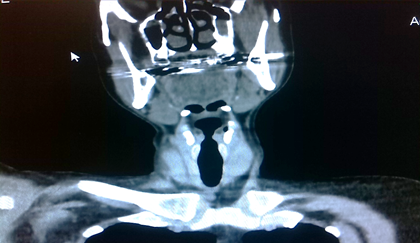

Pruebas de laboratorio: se aprecia leucocitosis en 12.000cel/mm3 y luego progresa a 24.500cel/mm3, polimorfo nuclear 90%, valores de glucosa en sangre elevada. Se le realiza rayos x de cuello (Figura 2. Anexos), y ecosonograma de región cervical, donde se describe una lesión ocupante de espacio alrededor de la tráquea hacia el lado izquierdo, de 4x 2 cm, heterogénea de bordes bien circunscritos. No presenta vascularidad al uso del Doppler. El lóbulo izquierdo del tiroides, muestra efecto de masa en su cara inferior. Concluye con una lesión ocupante de espacio en región traqueal izquierda sugerente de absceso frio. Se le realiza estudio de tomografía computarizada de cuello (Figura. 3, 4, 5. Anexos), y tórax, apreciando en región lateral izquierda del cuello, hiperdensidad paralela a la tráquea y glándula tiroidea, haciendo efecto de masa compresiva sobre las estructuras cercanas.

IMG_20181019_155434

Figura 4. Tomografía axial computarizada de región cervical. apreciando en región lateral izquierda del cuello, hiperdensidad paralela a la tráquea y glándula tiroidea, haciendo efecto de masa compresiva sobre las estructuras cercanas.

Fuente: Fotografía realizada por Dra. María Pulgar.